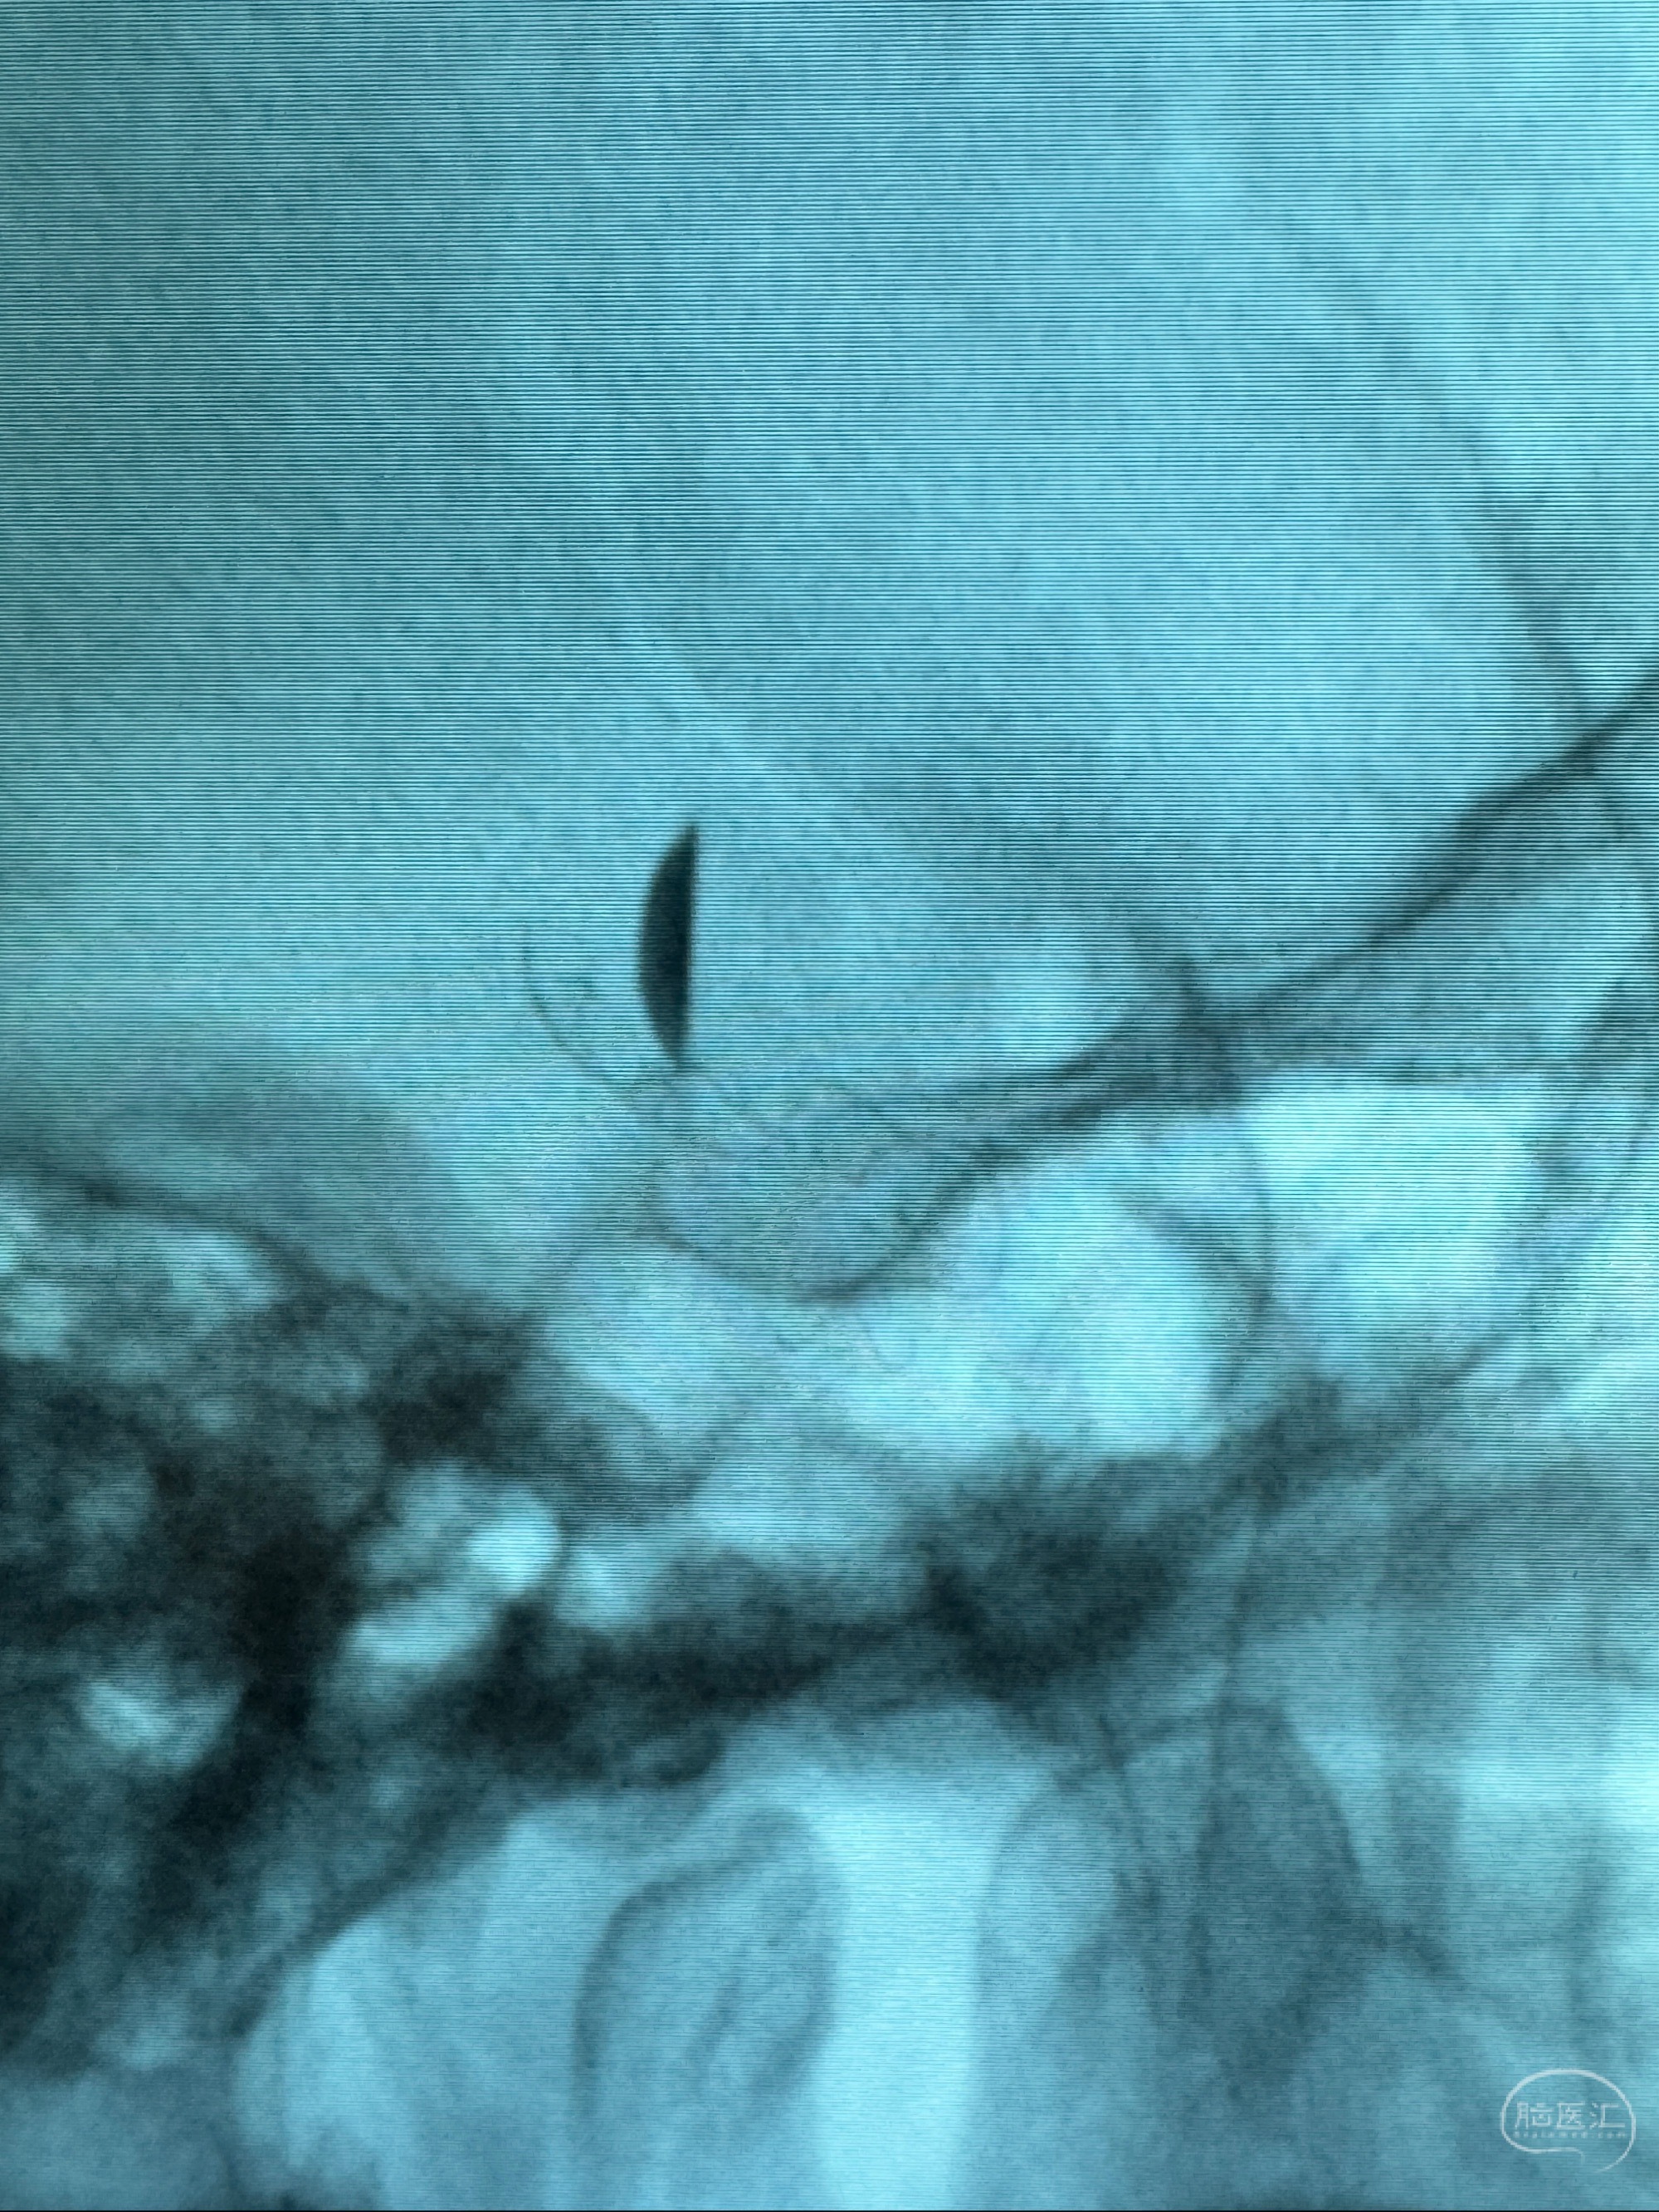

透视可见红圈部分为支架导管的头端

手推冒烟显示支架位置及展开情况,箭头为支架导管的位置

尝试回收支架失败,只能考虑释放支架了

逐帧图像展示歪着脖子释放支架,旁边吩咐助手手机摄影、拍照留像(透视机不能留影像)